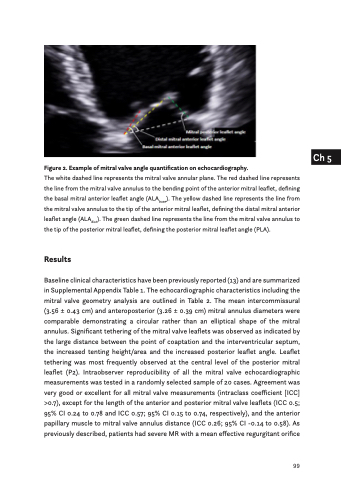

Figure 2. Example of mitral valve angle quantification on echocardiography.

The white dashed line represents the mitral valve annular plane. The red dashed line represents the line from the mitral valve annulus to the bending point of the anterior mitral leaflet, defining the basal mitral anterior leaflet angle (ALAbase). The yellow dashed line represents the line from the mitral valve annulus to the tip of the anterior mitral leaflet, defining the distal mitral anterior leaflet angle (ALAdist). The green dashed line represents the line from the mitral valve annulus to the tip of the posterior mitral leaflet, defining the posterior mitral leaflet angle (PLA).